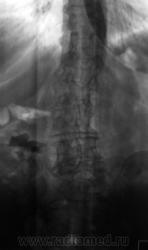

Чуть обработанные изображения.

Очень мелко и, поэтому, сложно разобрать на что указывает стрелка. Возможно, там еще один конкремент... Да, кстати, в заключение бы еще добавить дистопию почек. Странно что у Вас "пользовали" бабку (почему-то мне кажется что это не девочка) по вертебральной патологии без рентгенологического исследования.

По принципу "меньше знаешь -крепче спишь", видимо уже совсем беспокоить начало В нерешительности, а по поводу дистопии рано говорить с учетом возраста и не полного дообследования надо думать о нефроптозе, кстати контуры правой почки четко визуализируются.

Да, по косвенным признакам, возможность правостороннего нефроптоза протокольно отметили.